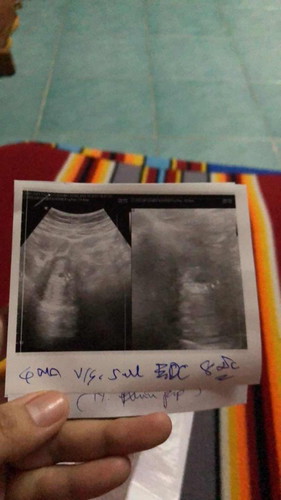

เสี่ยงหลุดเนื่องจาก รกเกาะต่ำ

มีแม่ๆ ท่านไหนเคยเจอประสบการณ์ รกเกาะต่ำบ้างไหมคะ ตอนแรกกังวลกลัวไม่ท้อง พอท้อง100% หมอบอกให้ระวังเสี่ยงหลุดเพราะน้องเกาะต่ำมาก ผ่าน 12 สัปดาห์ ไปได้ไข่ถึงจะฝังตัวสมบูรณ์ #ท้องแรกคะ #ขอบคุณสำหรับคำตอบค่ะ